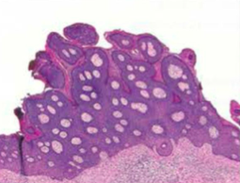

Serous/Mucinous Surface Epithelial Ovarian Tumors

Serous (watery, 80%) vs. mucinous (mucus, 20%) based on what fills the cyst Benign (cystadenoma): single cysts, flat lining, premenopausal vs. Malignant (cystadenocarcinoma): complex, thick/shaggy lining, postmenopausal vs. Borderline: between benign/malignant *BRCA1 mutation --> risk of serous carcinoma of the ovary and fallopian tubes